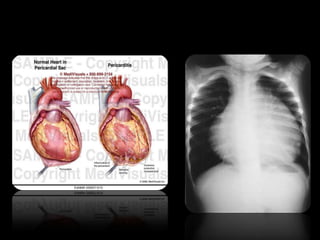

Pericardio seroso.

Es la capa interna del pericardio

que se halla constituida por dos

hojas, que se hallan separadas

por el espacio pericárdico, lleno

de una pequeña cantidad de

líquido pericárdico que sirve

para adherir firmemente las dos

hojas, pero que facilita su

deslizamiento.